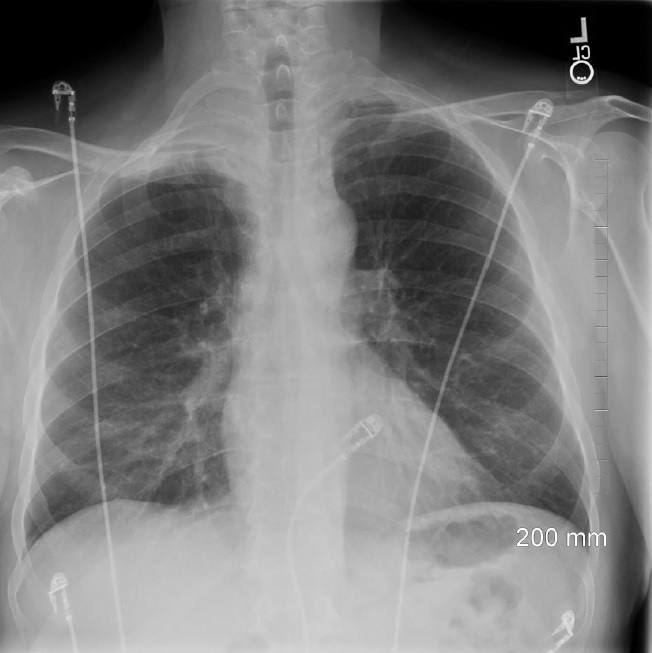

Pancoast tumor